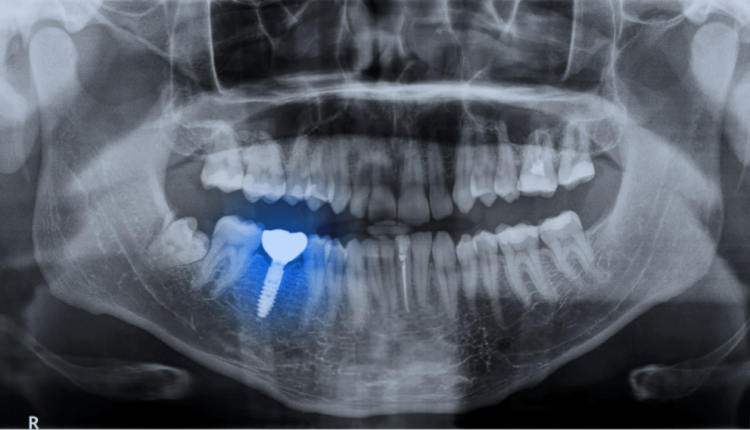

Can I get implants with bone loss?

Even if you’ve lost all your teeth and noticed your cheeks starting to sink inward, a sign of jaw bone loss, you may still not need a bone graft to support your dental implants. During your initial consultation, your dentist will take 3D images of your mouth, including your jaw.